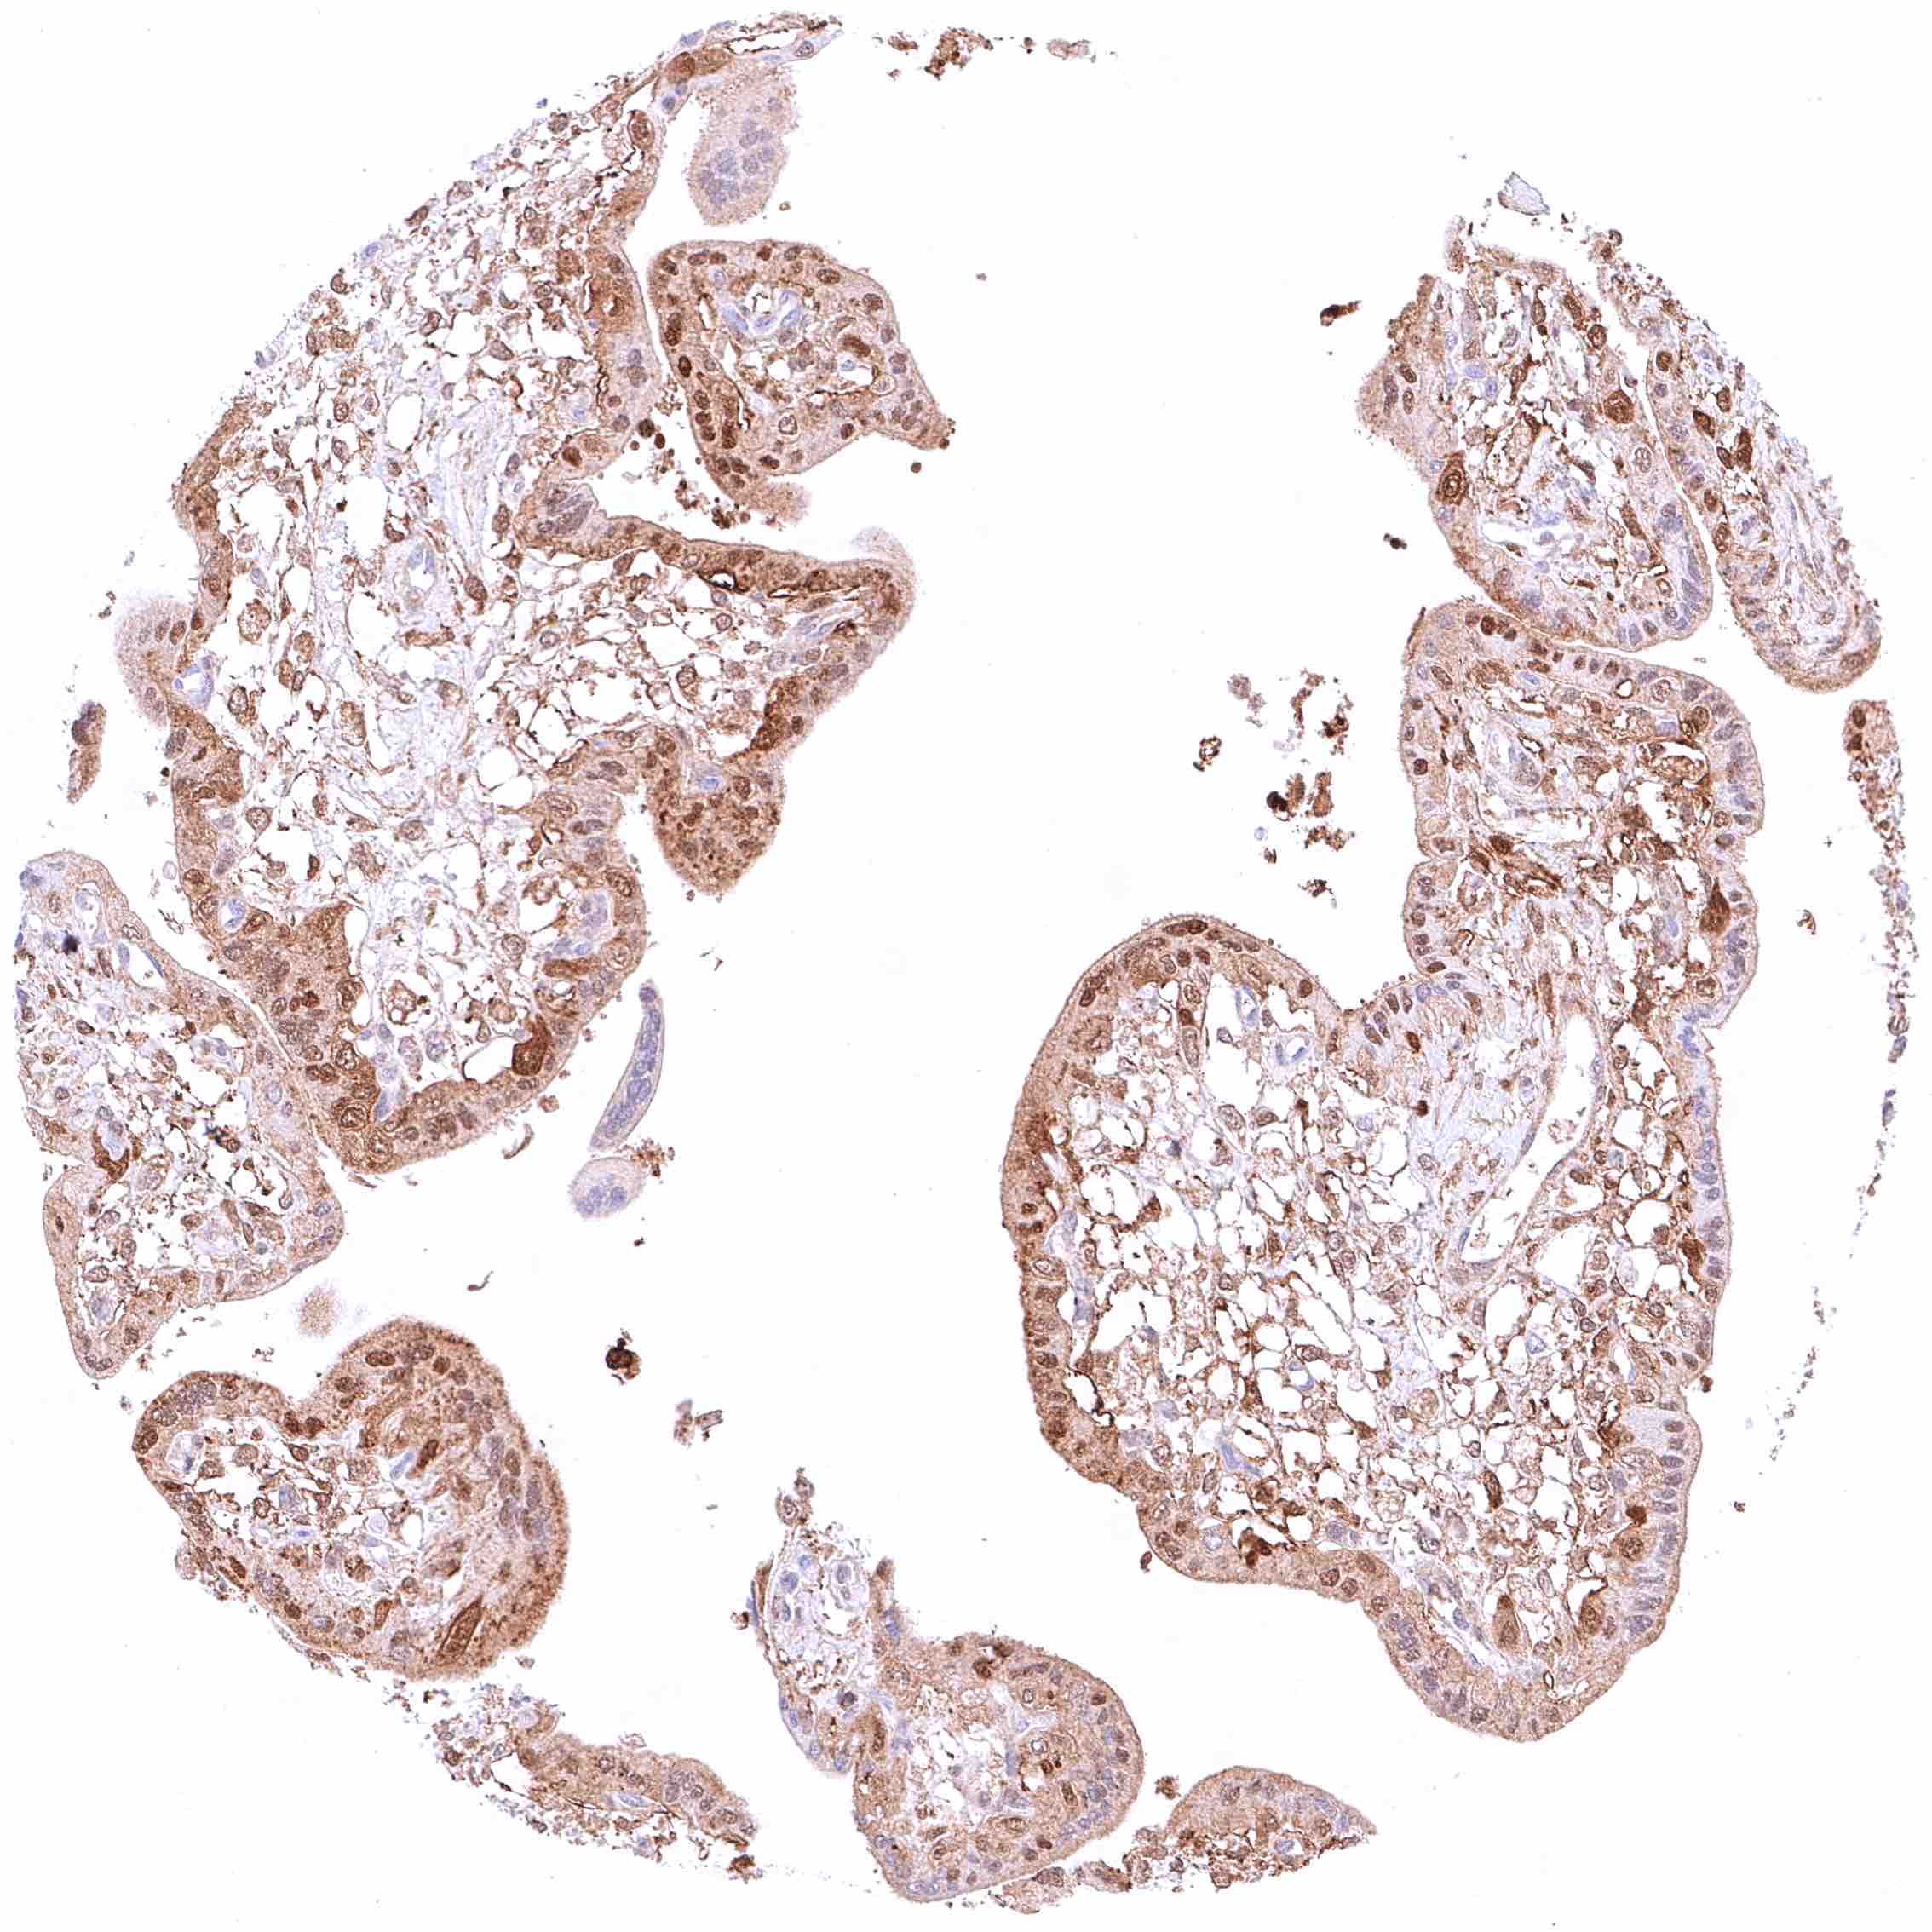

Prostate – Intense nuclear and cytoplasmic GSTP1 staining of basal cells while staining is faint or absent in acinar cells

Prostate – Intense nuclear and cytoplasmic GSTP1 staining of basal cells while staining is faint, weak or even absent in acinar cells